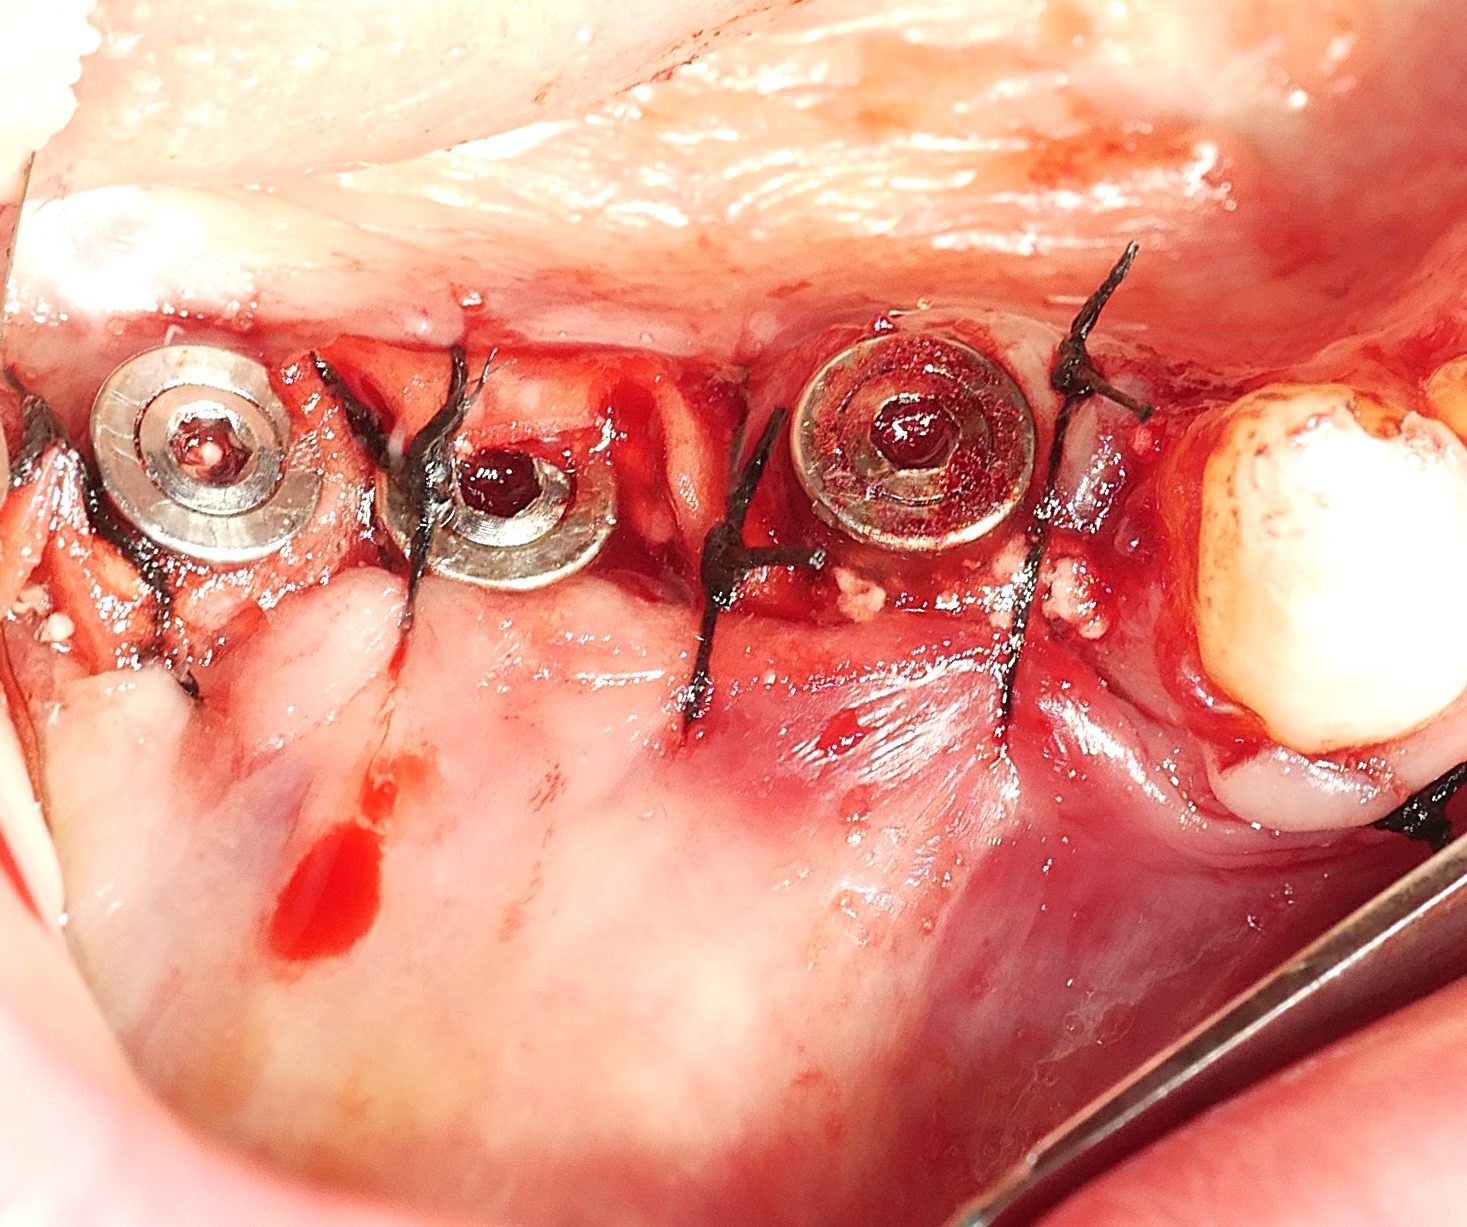

Clinical relevance is further reinforced by Božić et al. (2021), who reported significant improvements in CAL gain and PPD reduction when cross-linked HA was applied in combination with porcine bone graft in intrabony defects. These results support the hypothesis that HA not only serves as a scaffold but also modulates local wound healing biology by favoring fibroblast and osteogenic cell recruitment.

Hard and soft tissue augmentation by fibroblastic stimulation

Taken together, this body of evidence positions cross-linked hyaluronic acid as a promising and versatile bioactive tool in oral regenerative procedures. Unlike other more complex or expensive biological agents, HA provides a straightforward and reproducible clinical approach. It supports soft and hard tissue healing, modulates inflammation, and now, as shown, actively promotes cementoblastic and fibroblastic functions essential for successful periodontal and peri-implant regeneration.